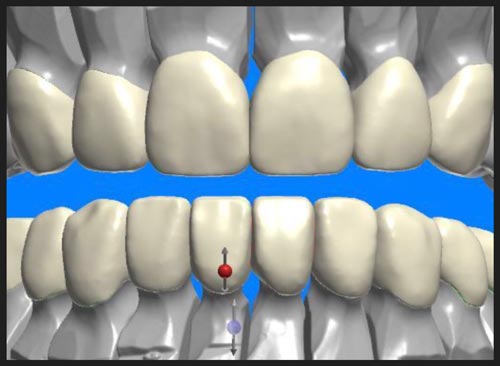

Biting surface realignment can be achieved through traditional orthodontics (long term), orthognathic surgery (costly and time-consuming), and custom fabrication of dental components (crowns) that effectively reconfigure and shift the occlusal surfaces.

Adjusting Bite Dynamics

The repositioned lower teeth were then fitted with either veneers or custom crowns to optimize the positioning of biting surfaces between the upper and lower jaw.

The adjacent picture shows the actual crowns and veneer products that were used to alter the biting surfaces of nearly every tooth in the lower jaw as a means for addressing the patient’s crossbite issue.

The combination of short-term orthodontic straightening and bite opening moved the jaw into the position that Mother Nature failed to produce. Lastly, Dr. Nazarian’s choices of veneers and porcelain crowns on different tooth structures assure that occlusion-caused breakage will not occur.